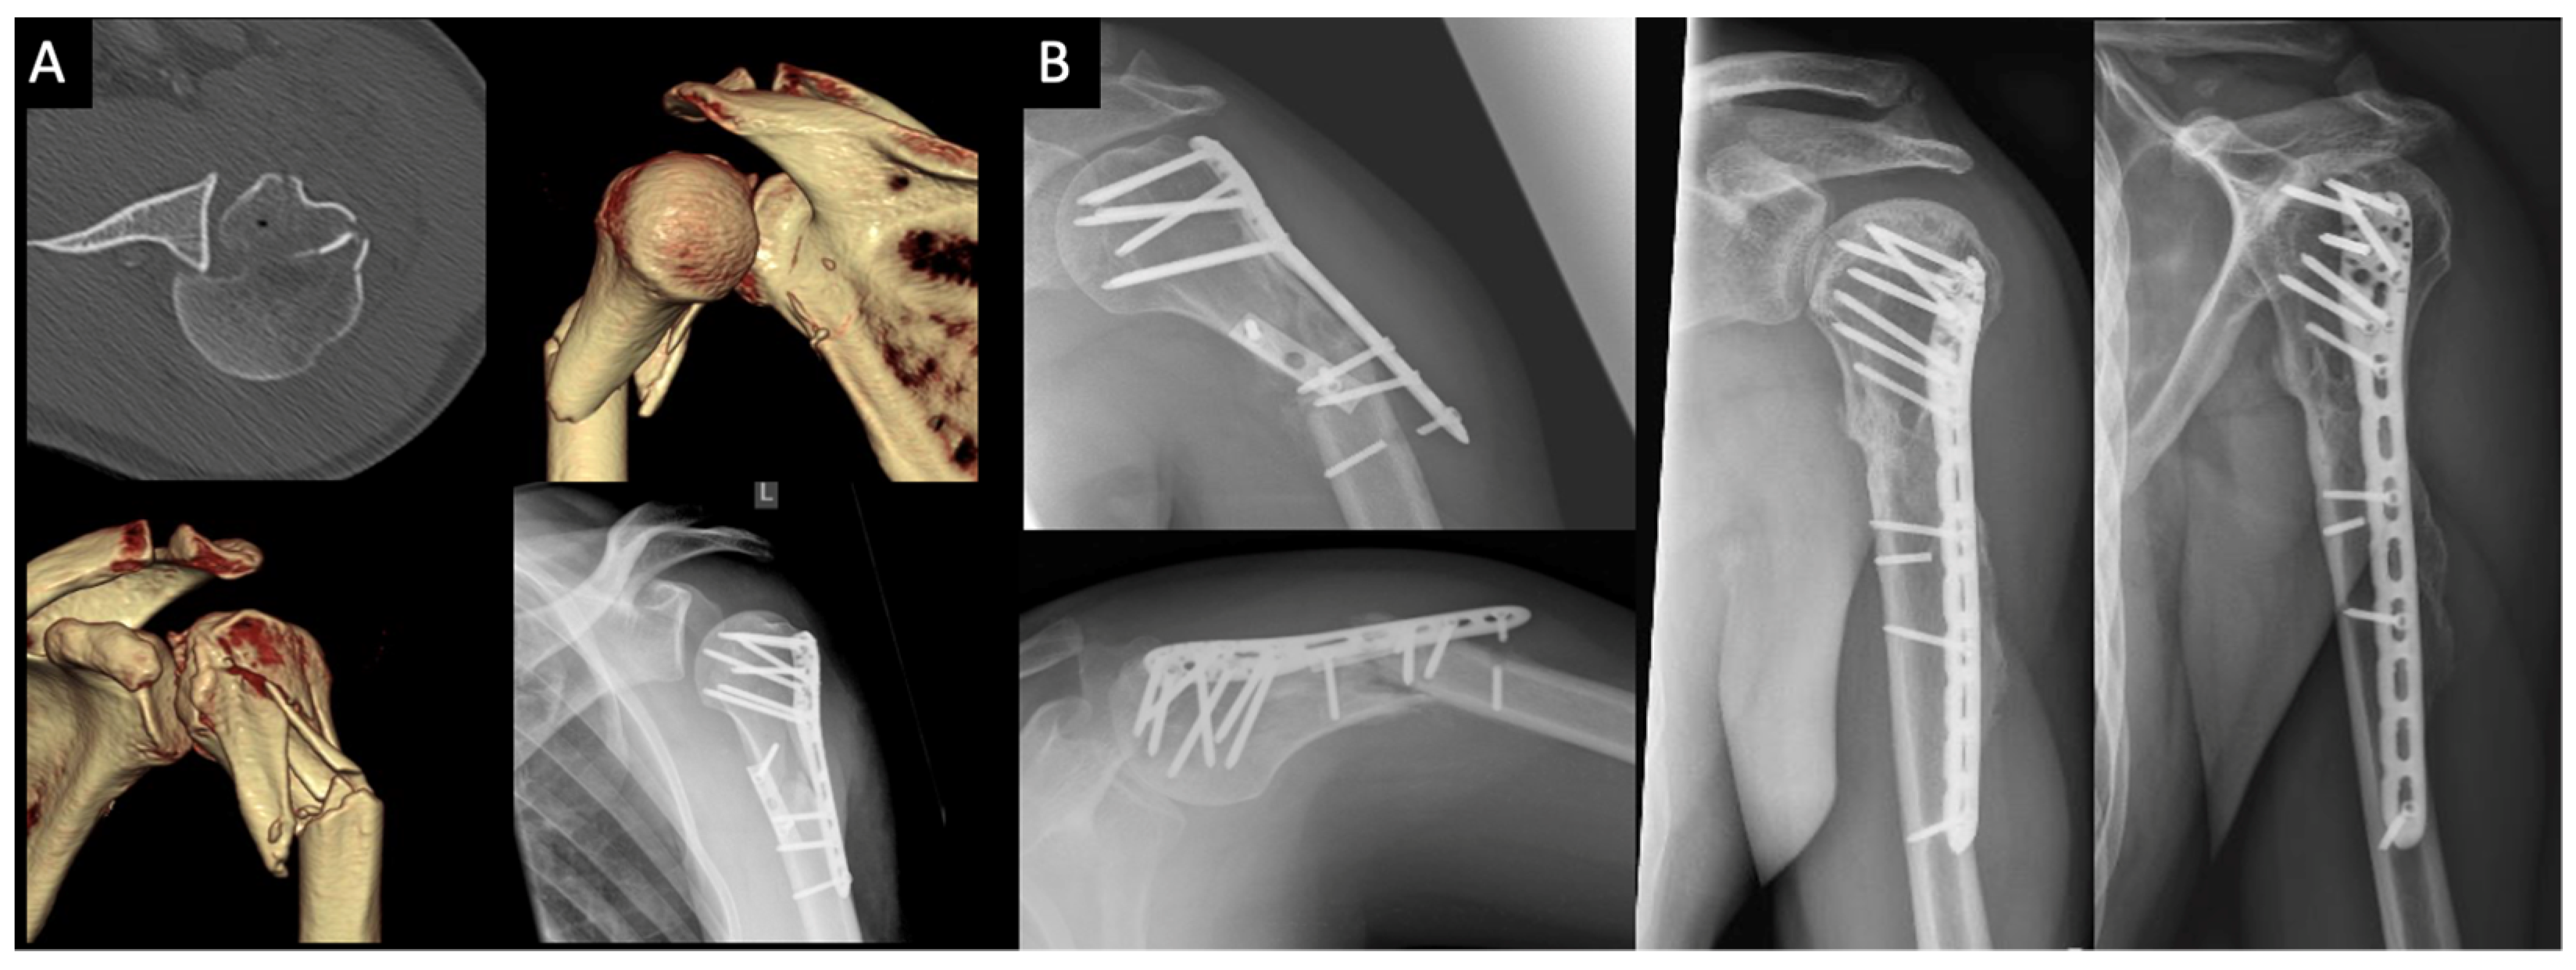

3.1. Impression Type Fractures (ITFs)

3.2. Surgical Neck Fractures of the Humerus (SNFs)

| 13 | 39 | M | SNF | DPO | 5.9 |

| 14 | 48 | W | SNF | DPO | 2.7 |

| 15 | 68 | M | SNF | Allo- and autograft, 2x screw, SPO | 2.2 |

| 16 | 47 | M | SNF | 2x screw, SPO | 2.3 |

| 17 | 45 | M | SNF | Autograft, 2x screw | 4.2 |

| 18 | 60 | W | SNF | SPO, 2x screw | 2.5 |

| 19 | 58 | M | SNF | Autograft, SPO, 1x screw | 2.1 |